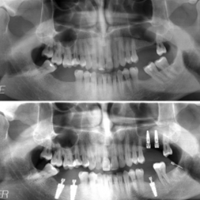

Vi erbjuder allmäntandvård, implantat, estetisk tandvård, tandblekning, tandställningar och kirurgi med mera. Dina tänder och leende är en del av ditt välmående och vi värnar om just din hälsa och livskvalitet.